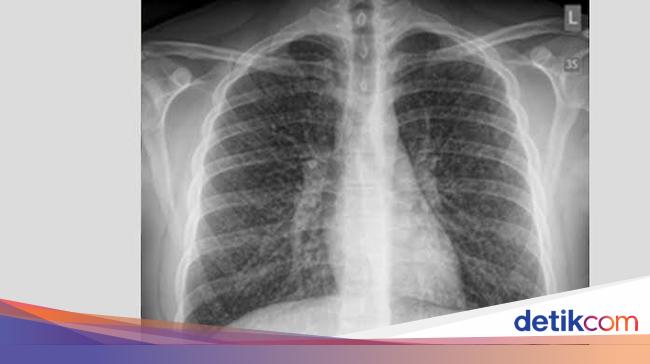

Seperti rokok konvensional, vape dan rokok elektrik juga membawa sederet bahaya. Salah satunya, memicu kondisi 'popcorn lung' saluran udara di paru mengecil.